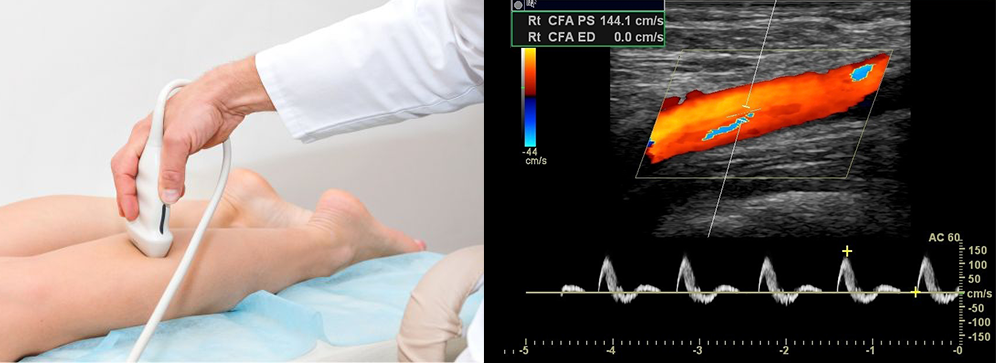

If you're experiencing leg swelling, cramps, or unusual coldness in your limbs, an Arterial or Venous Doppler test may be the key to early diagnosis. At our advanced diagnostic centre in Pallavaram, we provide highly accurate Doppler ultrasound services to assess blood flow in both the upper and lower limbs. This non-invasive, real-time imaging technique helps detect conditions like deep vein thrombosis (DVT), peripheral artery disease (PAD), and varicose veins, offering timely insight into vascular health.

An arterial and venous Doppler test is a specialized ultrasound technique that uses sound waves to assess the flow of blood through arteries and veins. In the context of limbs, this test is conducted on either the upper limbs (arms) or the lower limbs (legs) to identify blockages, narrowing, or clots. Unlike traditional X-rays, Doppler ultrasound does not involve radiation and is considered very safe and highly effective in vascular evaluation.

For the arterial Doppler, the focus is on checking for adequate blood flow from the heart to the limbs through arteries. For the venous Doppler, it helps detect whether veins are allowing blood to return efficiently to the heart. The combination of both provides a comprehensive picture of circulatory health in the limbs.

Once the test is completed, our radiologist will analyze the blood flow waveforms and create a detailed report. This will be shared with your referring doctor for further treatment planning. We also maintain electronic records for easy access during follow-ups.